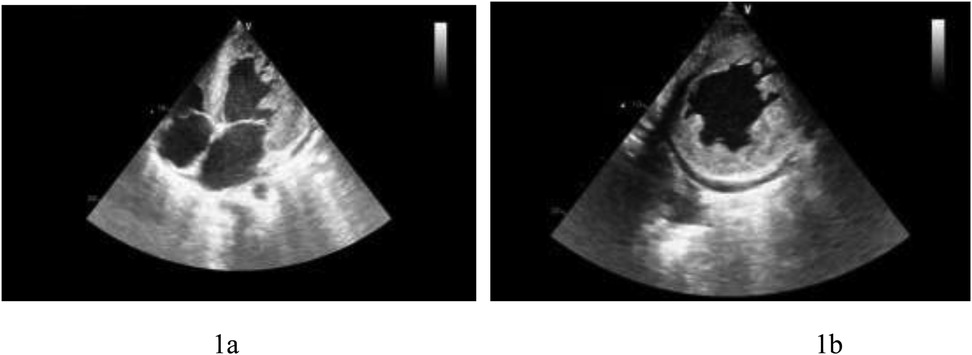

Echocardiography: myocardial involvement [interventricular septum (IVS): 2.16 cm, left ventricular posterior wall (LVPW): 2.39 cm], left ventricular enlargement (LV: 6.6 cm), mild to moderate mitral regurgitation, mild tricuspid regurgitation, mild pulmonary hypertension, significantly reduced left ventricular function (EF: 20%), and a small amount of pericardial effusion. Significant trabeculae in the middle segment of the left ventricular free wall and the apical segment of the left ventricular wall were visualized, showing a “honeycomb-like” change. The ratio of the thickness of the non-compacted myocardium (∼16 mm) to the thickness of the compacted myocardium (∼8 mm) at the end of contraction was ∼2:1. Color Doppler ultrasound detected low-speed blood flow in the gaps between the myocardial recesses that communicated with the left heart cavity (Figure 1).

Figure 1

(a) Left ventricular apical four-chamber view showing left ventricular thickening and hypertrabeculation. (b) Left ventricular short-axis view presenting left ventricular thickening and hypertrabeculation.